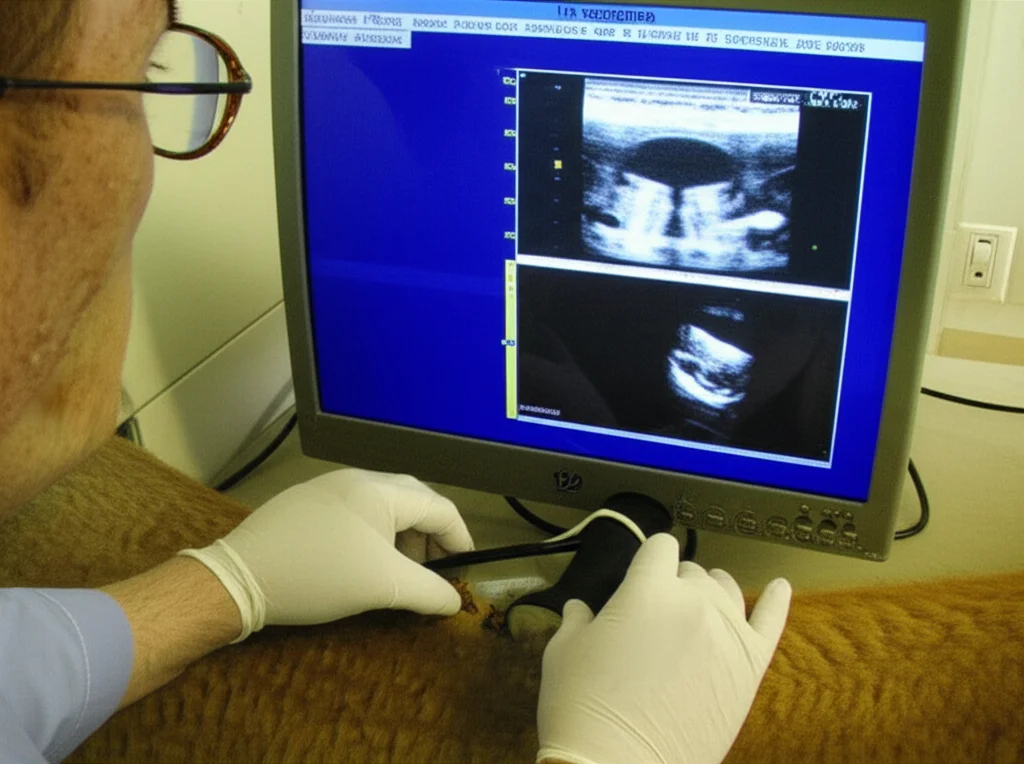

- Esami ecografici: prima dell’iniezione e poi settimanalmente, usando una sonda lineare ad alta risoluzione (10-13 MHz) posizionata sulla superficie interna delle labbra.

L’ecografia: il nostro occhio hi-tech

E l’ecografia? Ha mantenuto le promesse! Le immagini ecografiche hanno rivelato chiare modifiche strutturali negli strati tissutali delle labbra dopo l’iniezione di BOTOX. Già al settimo giorno, entrambi i gruppi trattati con BOTOX mostravano un aumento delle regioni ipoecogene (più scure nell’immagine ecografica) nel tessuto sottocutaneo, segno di edema o reazione tissutale. Questi cambiamenti erano più pronunciati nel gruppo con 200 IU e persistevano fino al quattordicesimo giorno, per poi diminuire gradualmente entro il ventottesimo giorno.

Le misurazioni dello spessore tissutale ottenute con l’ecografia erano perfettamente allineate con le osservazioni morfologiche. L’aumento massimo dello spessore è stato registrato al settimo giorno nel gruppo con 200 IU (circa 23.5 mm!). Entro il giorno 54, lo spessore in entrambi i gruppi BOTOX ha iniziato a normalizzarsi, pur rimanendo leggermente elevato rispetto ai valori basali. Nel gruppo di controllo, invece, non c’erano variazioni significative. L’ecografia si è dimostrata quindi preziosa anche per rilevare la fibrosi muscolare che può derivare da iniezioni ripetute di tossina botulinica.

Una cosa che ci ha colpito è stata l’osservazione di una disposizione irregolare delle fibre muscolari nella prima settimana post-iniezione, un dettaglio che solo l’ecografia poteva svelare con tale precisione.